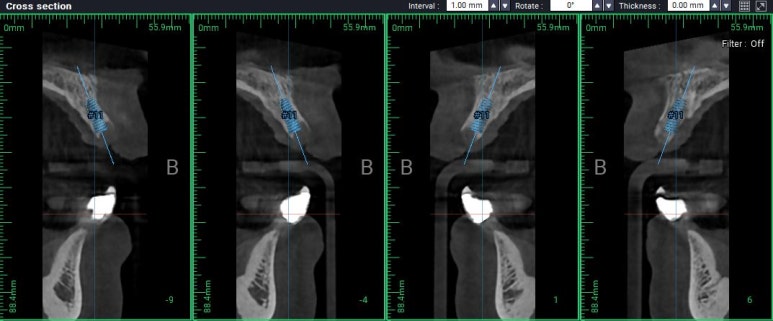

이런 식으로 가운데 남은 적은 양의 잇몸뼈 인에 임플란트 두개를 나란히 심기로 계획을 하였구요,

이건 위턱 오른쪽 가운데 앞니 부위 임플란트를 배열한 단면,

이건 위턱 왼쪽 가운데 앞니 부위 임플란트를 배열한 단면입니다.

다행히도 남아있는 뼈의 양은 임플란트 두개를 담기에 딱 맞는 공간이었습니다.

남은뼈가 굉장히 적었기 때문에, 치과용 치근단방사선사진을 촬영해가며 그 위치를 설정하였습니다.